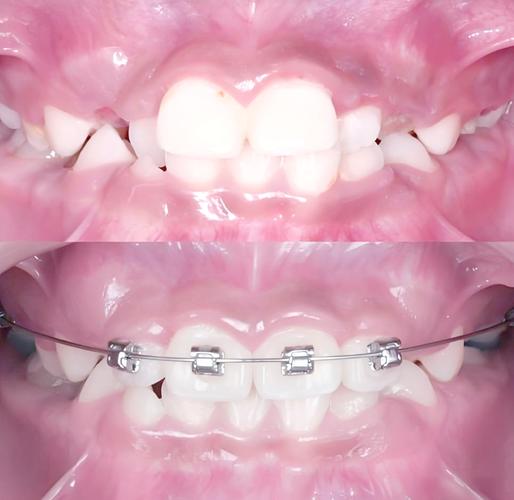

口内照片对比

- 治疗前:正观可见前牙反颌(上牙咬在下牙内侧),反覆盖大(下前牙唇侧与上前牙舌侧距离大);侧观可见上牙弓狭窄,后牙反颌可能存在。

- 治疗后:正观前牙覆颌、覆盖正常,咬合关系稳定;侧观上牙弓宽度增加,后牙反颌纠正,磨牙关系达中性。